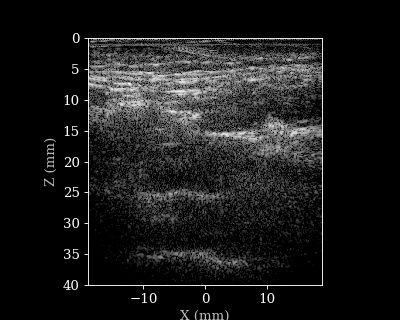

We will load a sequence of acquired RF data frames (carotid scan) and reconstruct a B-mode image from each frame. We will then animate the sequence of images. But first let’s load the data and parameters.

Reconstructing a sequence of B-mode images

animate_images(images, "./bmode_sequence.gif", scan, interval=100, cmap="gray")

15/15 ━━━━━━━━━━━━━━━━━━━━ 3s 124ms/step

B-mode sequence